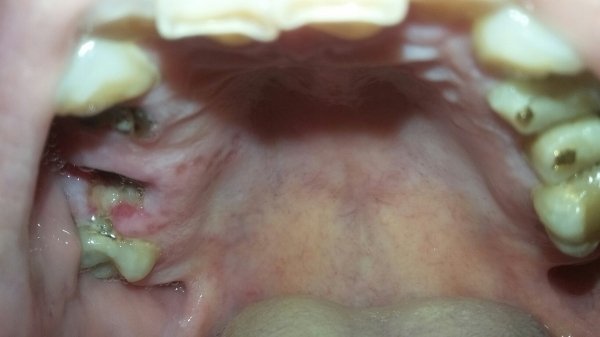

В десне в самом низу появились два твердых шарика, они не двигаются. Если провести пальцем по десне между щекой и десной, то они ощущаются, но дискомфорта нет. 2 года назад в этом месте мне удалили зуб (нижний 6), иногда десна воспаляется после холодного и опухает, появляется гной.

Вам необходимо проделать рентген снимки и определить причину воспалений и экссудата. Уплотнения, как и воспаление, могут быть связаны с остатками корней после удаления. Обратитесь на прием к врачу, и все разрешится.